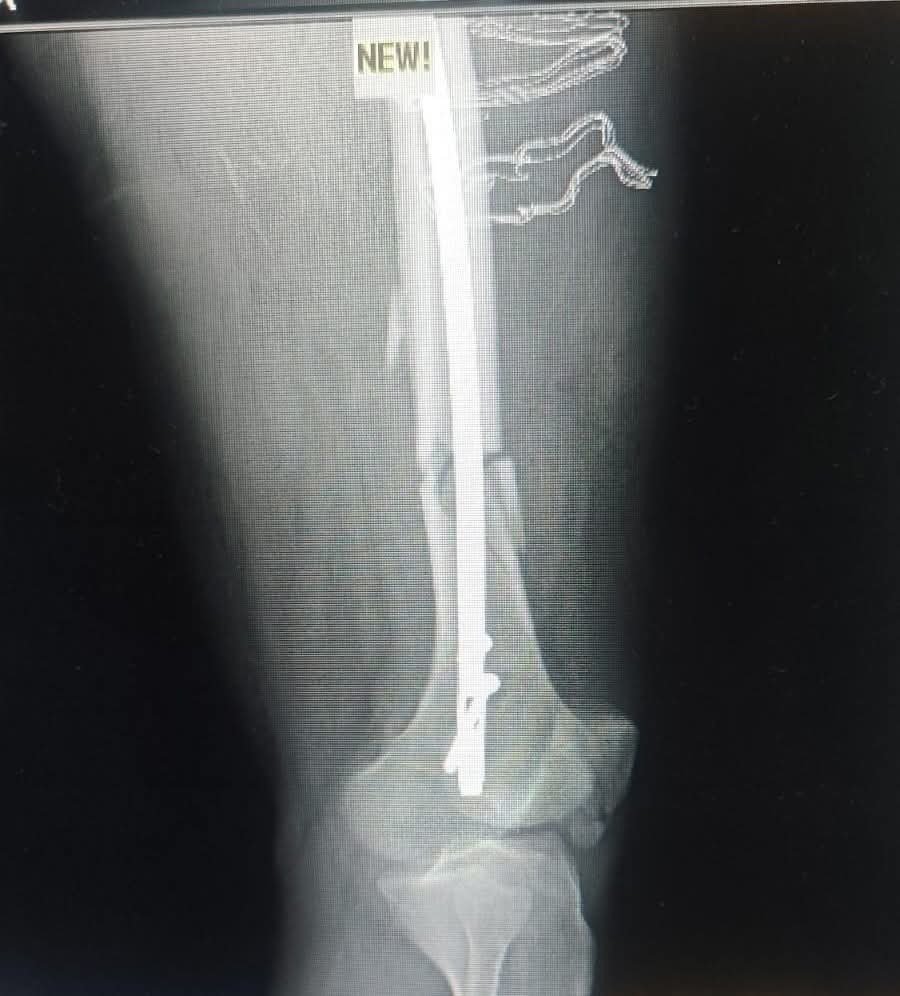

فقد استقبل قسم الطوارئ بالمستشفى المريض وهو يعاني من إصابات بالغة نتيجة الحادث. وبعد إجراء الفحوصات والأشعة الدقيقة، تبين وجود كسور متعددة شملت (عنق عظمة الفخذ، وعظمة الفخذ، وعظمة الرضفة "صابونة الركبة").

تثبيت كسر أعلى عظمة الفخذ باستخدام "مسمار نخاعي جاما" عالي الدقة.

تثبيت كسر أسفل عظمة الفخذ.

تثبيت عظمة الرضفة باستخدام مسمارين عبر فتحات جراحية صغيرة بالجلد (تدخل جراحي محدود)، مما يساهم بشكل كبير في تقليل الألم وتسريع فترة التعافي.